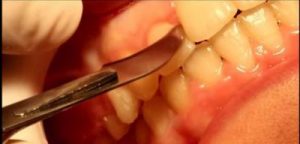

השיוף נעשה לצורך השגת מקום ליישור שיניים צפופות כאשר לא מעוניינים לעקור שיניים.

פעולה ניתוחית בה חותכים את הסיבים השטחיים שמחברים בין השן והחניכיים במטרה להקטין את הנטייה לחזרתה של השן למקומה המקורי לפני התזוזה האורתודונטית.